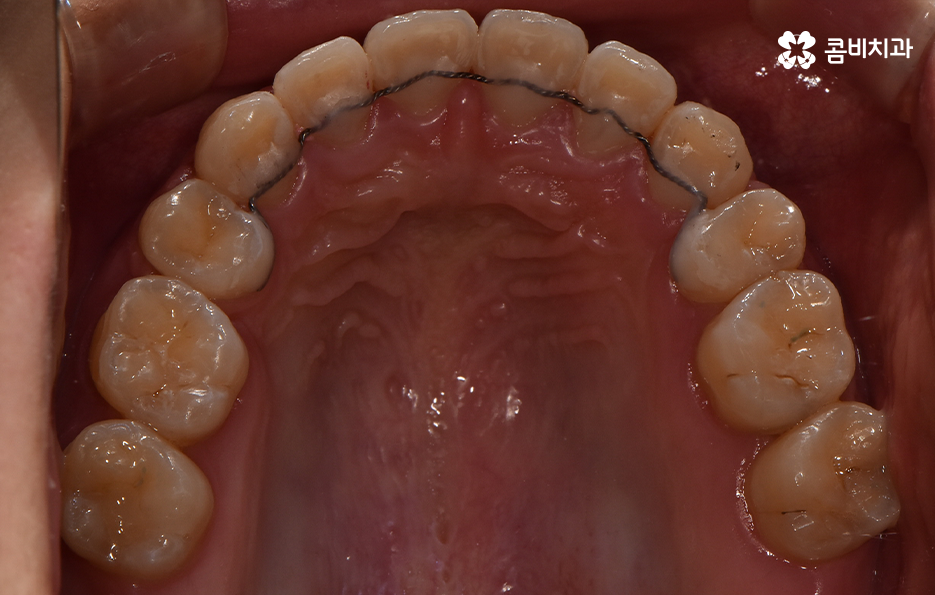

돌출입을 개선하기 위한 교정 치료의 사례에도 돌출입발치교정 사례가 많은 이유도 치아의 발치를 통해 앞니를 후방 이동시키는 치아 교정의 원리가 있기 때문이라고 설명할 수 있어요

이처럼 치열의 변화는 얼굴형 변화에도 많은 영향을 줄 수 있기 때문에 치아교정의 만족도는 치열뿐 아니라 환자 개개인의 골격과 얼굴형을 고려하여 잘 어울리는 조화적인 측면과 치아의 건강 등 고려해야 할 점이 많다는 것을 알 수 있는데요

오늘은 돌출입발치교정 통해서 치열도 가지런하게 교정하고 얼굴형의 변화뿐 아니라 교합까지 잘 맞물려서 건강하게 치아교정을 하는 방법에 대해 알아볼 거예요

환자 개개인의 치아 상태 및 골격, 얼굴형 등의 상태가 모두 다르기 때문에 돌출입의 경우 무조건 돌출입발치교정 만이 효과가 좋다고 말씀드리긴 어렵고 돌출입이 심하지 않은 경우에는 어금니를 후방 이동시키는 것으로 치료가 가능한 경우도 있어요

물론 어금니 후방 이동의 경우에는 사랑니를 발치해야 할 수 있고, 치료 기간이 길어질 수 있음을 말씀드리며, 치아교정의 원리로 볼 때 치아의 이동 공간이 있어야 치열을 가지런하게 펴는 등의 치료가 가능하다는 점이 포인트라 할 거예요